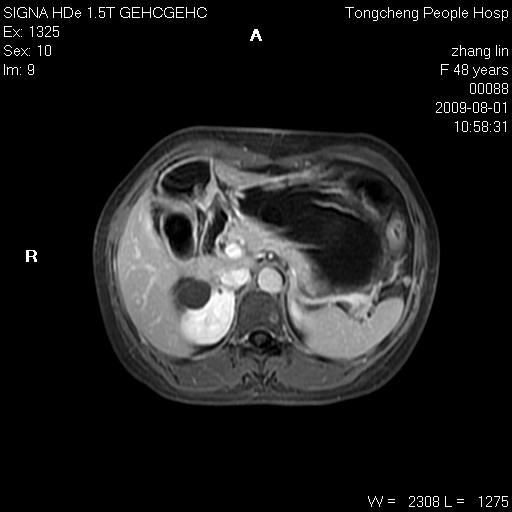

女,48岁。健康体检,彩超发现右肾占位性病变。平素健康。

临床诊断:右肾占位性病变,性质待定(囊肿?肿瘤?)。

上中腹部mr平扫+增强扫描,图像如下:

右肾上极见一类圆形病灶,t1wi呈等信号t2wi呈等高混杂信号,三期增强无强化,边界清---考虑囊肿出血。

同反相位均表现为等信号,病变无强化,考虑含蛋白的囊肿可能,弥散加权相或许有些帮助,

慢性胆囊炎